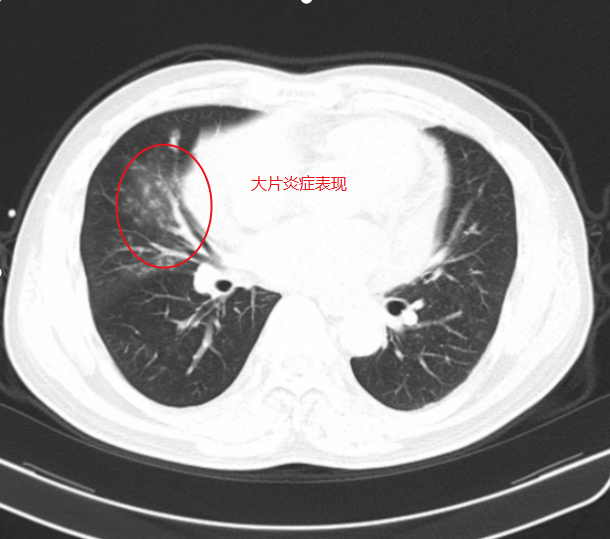

该患者因“咯血2天”入院,入院后医护人员迅速开展全面检查。胃镜检查未发现胃溃疡出血迹象,CT检查也未显示支气管扩张,但患者持续大量咯血,即便使用垂体后叶素等止血药物,病情仍未得到有效控制,甚至无法平卧,随时面临呼吸道堵塞、窒息的生命危险。面对这一危急情况,肿瘤科二区和麻醉科专家紧急会诊,综合评估后决定为患者实施经口支气管插管全麻下支气管动脉造影+栓塞术治疗。

▲入院CT见右下肺多发炎症,未见明显支气管扩张征象